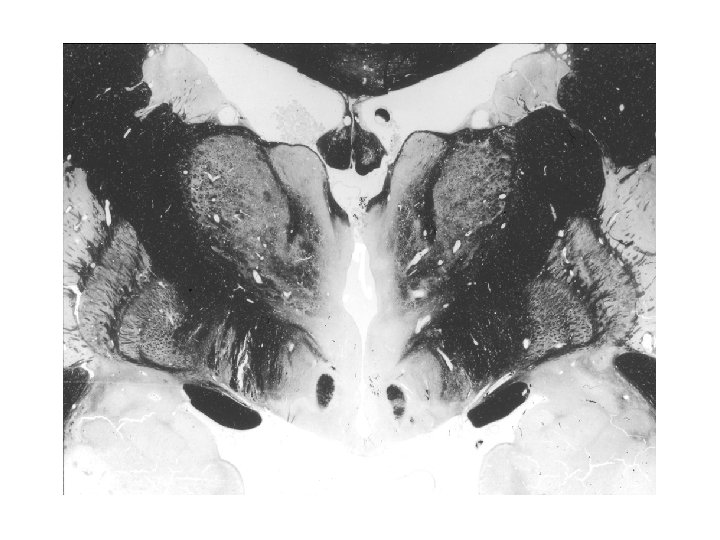

Nucleus paraventricularis hypothalami A hypothalamus egyik legjelentősebb magja, magno- és parvocellularis részre osztható. A magnocelluláris neuroszekretoros sejtek vasopressint és oxytocint termelnek, axonjaik a tractus hypothalamo-hypophysealis egy részét alkotják, és a hypothalamus hátulsó lebenyében végződnek. A parvocelluláris neuroszekretoros idegsejtek több peptiderg neurohormont (corticotropin-releasing hormon – CRH, thyrotropin-releasing hormon – TRH, vasopressin) és neuromodulátort (neuropeptidet) termelnek. A parvocellularis neuronok egy része az eminentia mediana portális erei révén juttatja el termékét a hypophysis elülső lebenyébe, másik részük a nyúltvelőbe és a gerincvelőbe projíciál. A CRH-termelő idegsejtek révén a paraventriculáris magot a stresszválasz központi részének, a „hypothalamohypophysis-mellékvesekéreg szabályozó rendszer” („HPA axis”) kiinduló pontjának tekintik.

PARAVENTRICULAR NUCLEUS - lesioning of the nucleus induces hyperphagia - hypoglycemia increases c-fos and CRH m. RNA expressions in the nucleus - paraventricular CRH increases sympathetic output and results in a long-lasting reduction of food intake (anorexic effect) - leptin activates neurons innervating the paraventricular nucleus - CRH 2 receptors mediate the inhibitory effect on feeding